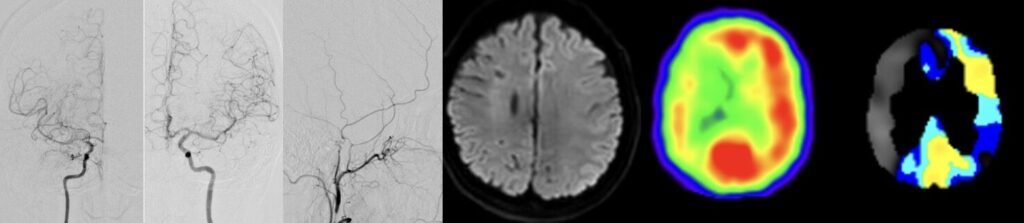

51歳女性の脳梗塞と脳室内出血を続けて起こした左片側もやもや病の患者さんをバイパス手術しました。STAがgaleaから外に出てGaleaの外に枝を出していたため皮弁翻展時にSTA頭頂枝が切れてしまい、端端吻合をしてからバイパスに用いました。2本とも無事開通しました。脳血流が著明に低下していたので術後の過灌流が心配で厳重な術後血圧管理を行いましたが、幸い順調な回復を見せています。

51歳女性の脳梗塞と脳室内出血を続けて起こした左片側もやもや病の患者さんをバイパス手術しました。STAがgaleaから外に出てGaleaの外に枝を出していたため皮弁翻展時にSTA頭頂枝が切れてしまい、端端吻合をしてからバイパスに用いました。2本とも無事開通しました。脳血流が著明に低下していたので術後の過灌流が心配で厳重な術後血圧管理を行いましたが、幸い順調な回復を見せています。